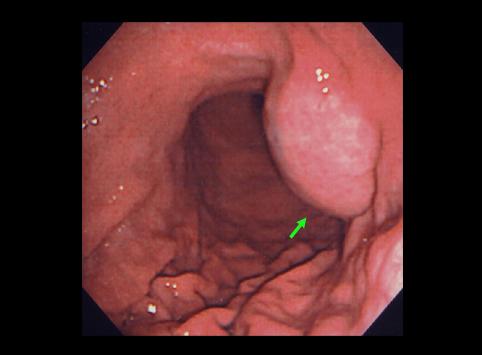

Ulcera Pustulosa con partición de Estómago

[Image-ID:7197]

Tumor no Epitelial Benigno/Quiste

estómago(región)/mas de dos

Endoscopia

40 -